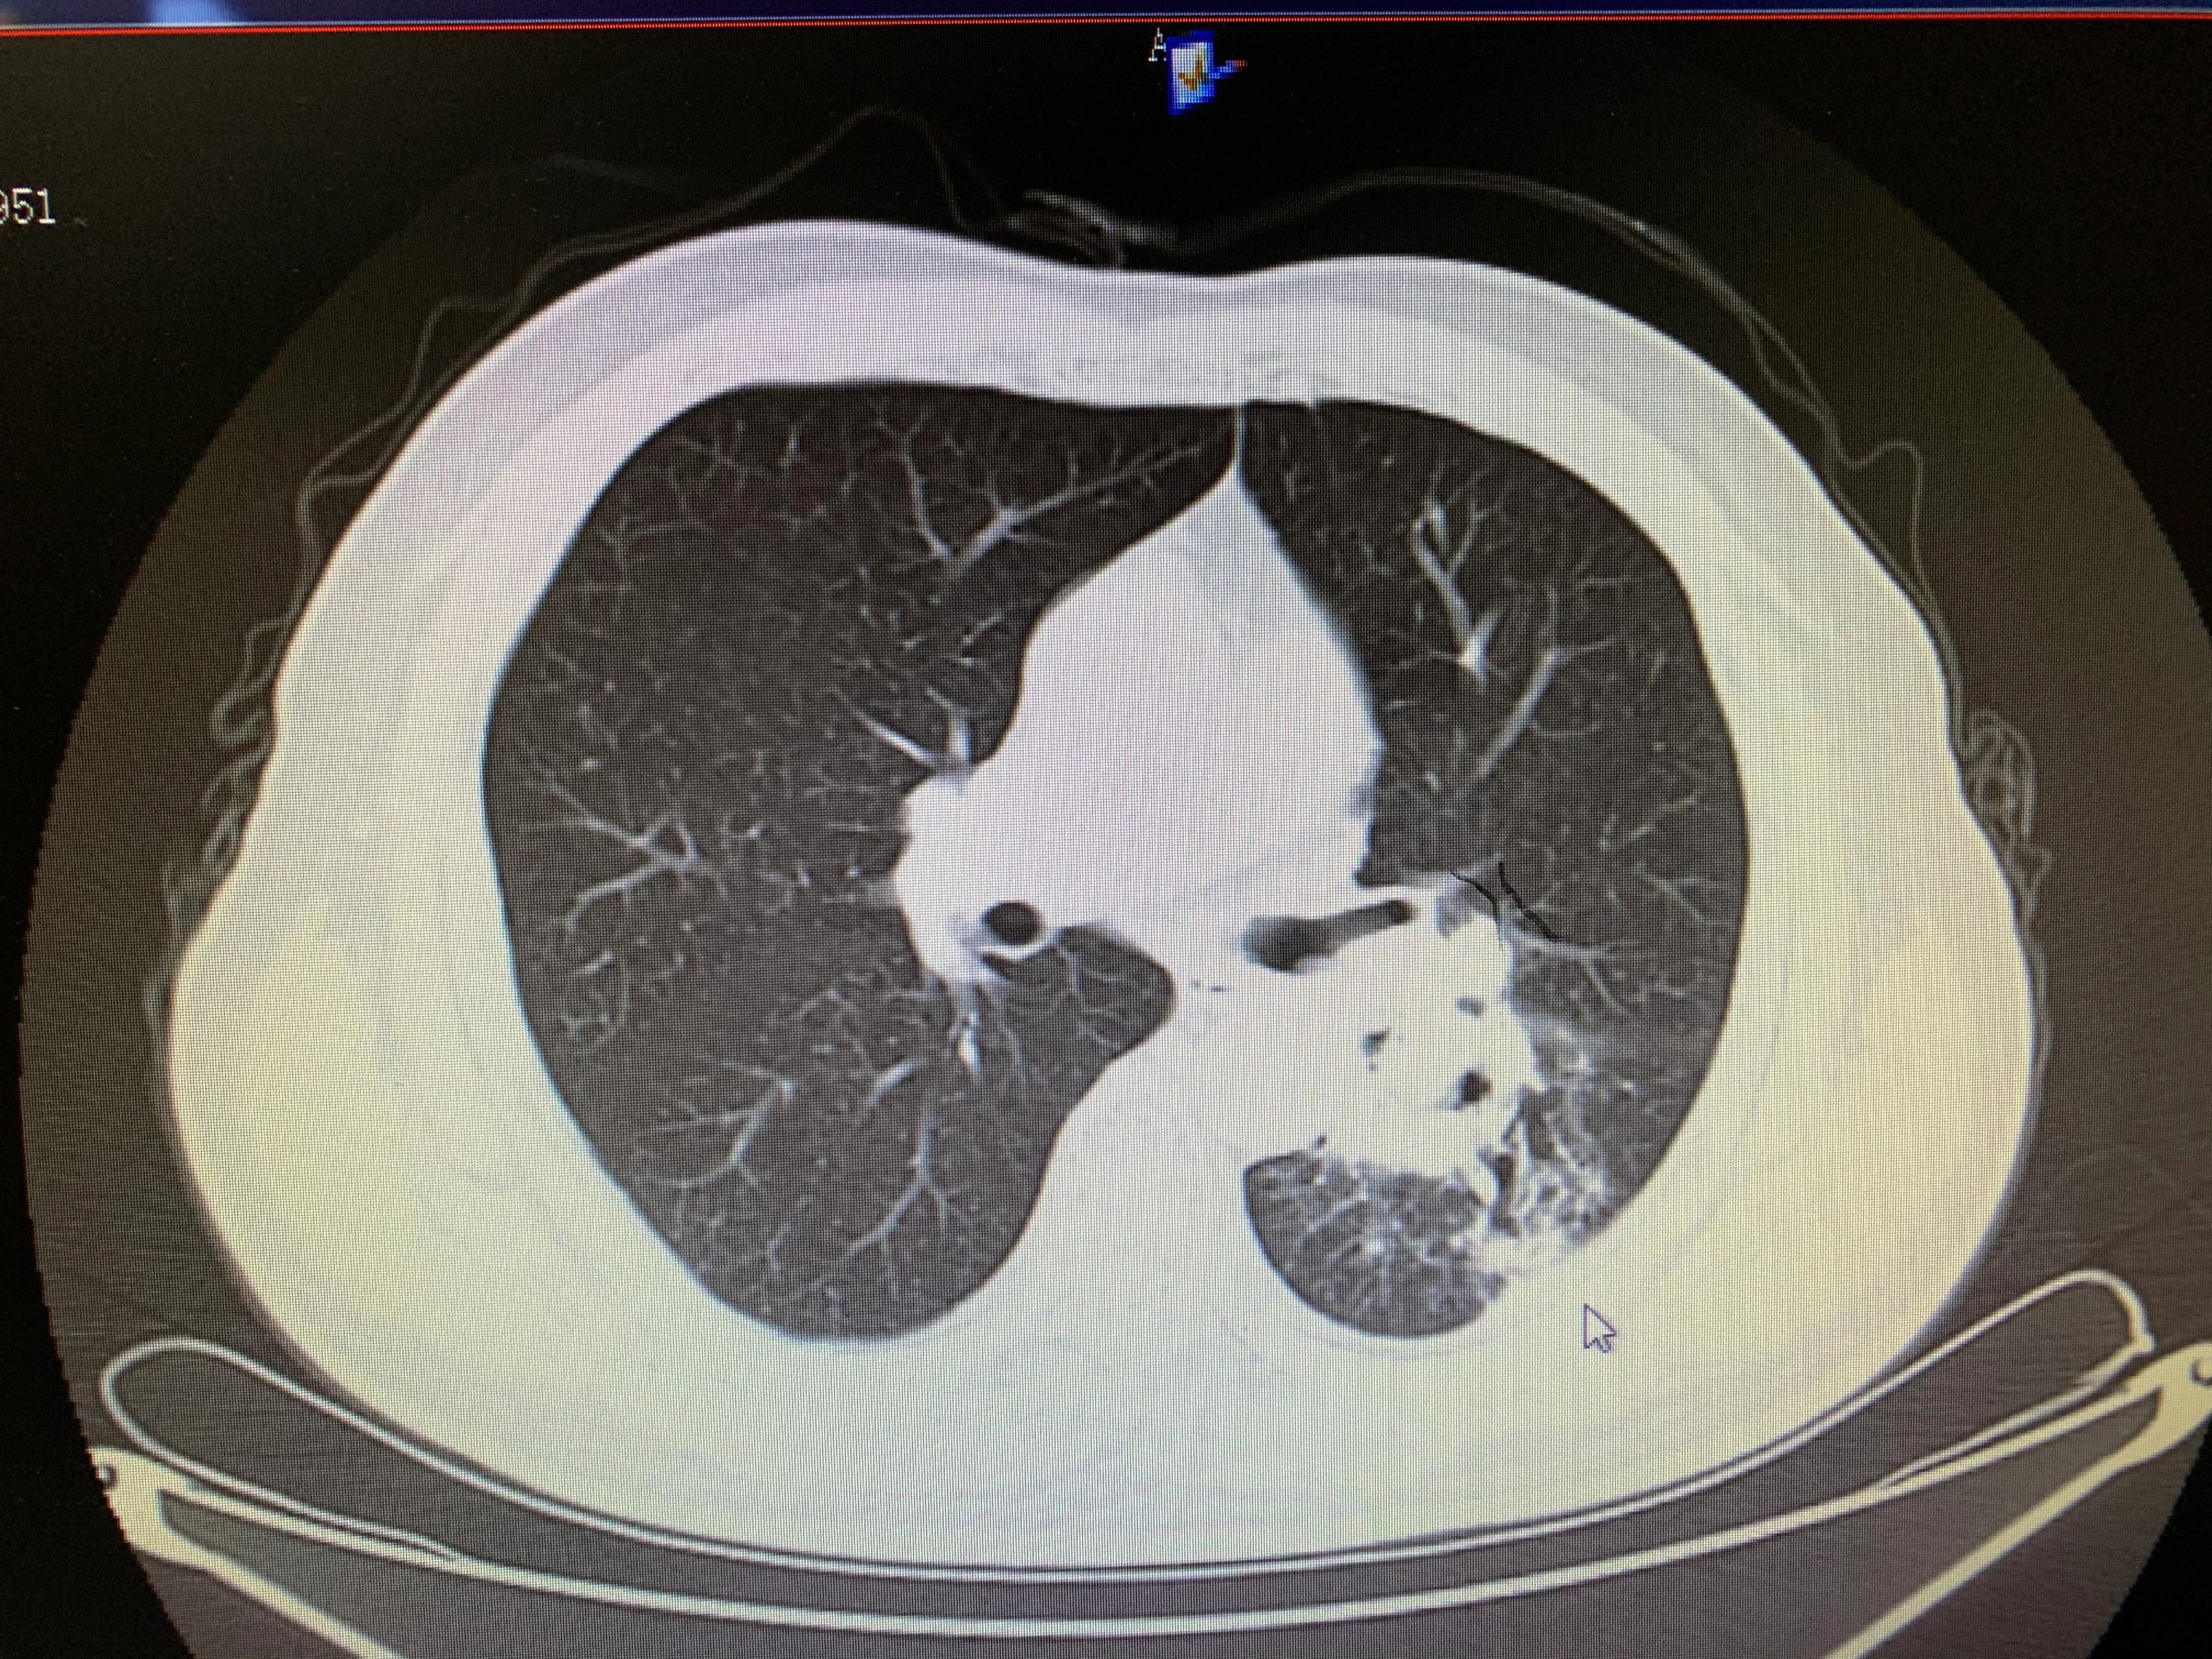

老年男性患者,左肺腺癌,化疗期间出现了咯血,术中可见左侧支气管动脉、左侧多支肋间动脉及左侧胸阔内动脉均参与肿瘤的血供,并可见以上动脉-肺动脉瘘,经肿瘤供血动脉灌注化疗药并且进行栓塞,术后未再出现咯血,一个月复查ct提示肿瘤较前明显减小,阻塞症状较前缓解。微创介入即经导管灌注化疗栓塞治疗肺肿瘤能够有效治疗肿瘤并且缓解肿瘤引起的一系列并发症,如咯血、阻塞性肺炎等,当然,肿瘤的治疗是综合治疗,需要多学科的共同参与。